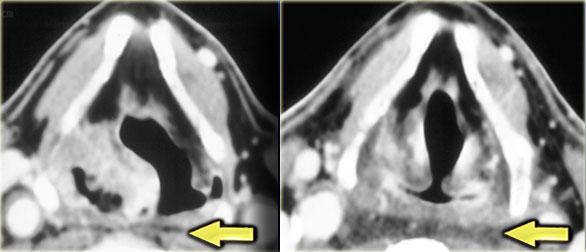

Bên trái là hai hình ảnh của một bệnh nhân bị ung thư xoang lê (đã trình bày trước đó).

Hình ngoài cùng bên trái cho thấy khối u xoang lê trước khi xạ trị.

Hình ảnh kế bên cho thấy đáp ứng hoàn toàn sau xạ trị.

Khoang sau hầu hiện đang bị giãn rộng và cho thấy tỷ trọng mô mỡ tăng lên do phù nề sau xạ trị.